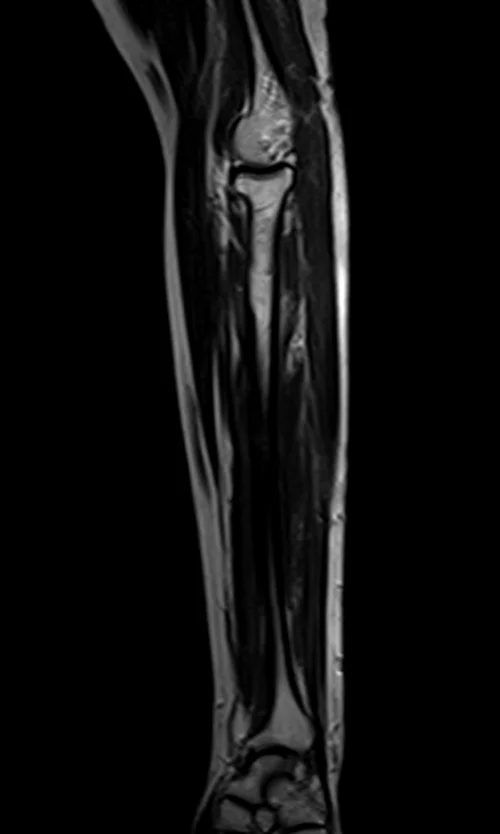

mri fore arm sagittal t2 image 1 - MRI